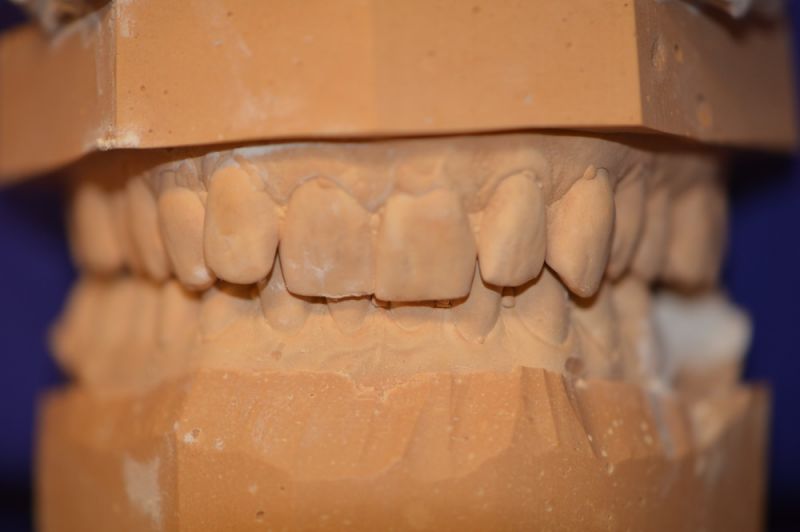

Es läuft dfas Nachweisverfahren einer CMD unter Einsatz eines adjustierten Aufbissbehelfs.

Deutlich erkennbar die Nonokklusion in neuromuskulär zenmtrierter Bisslage